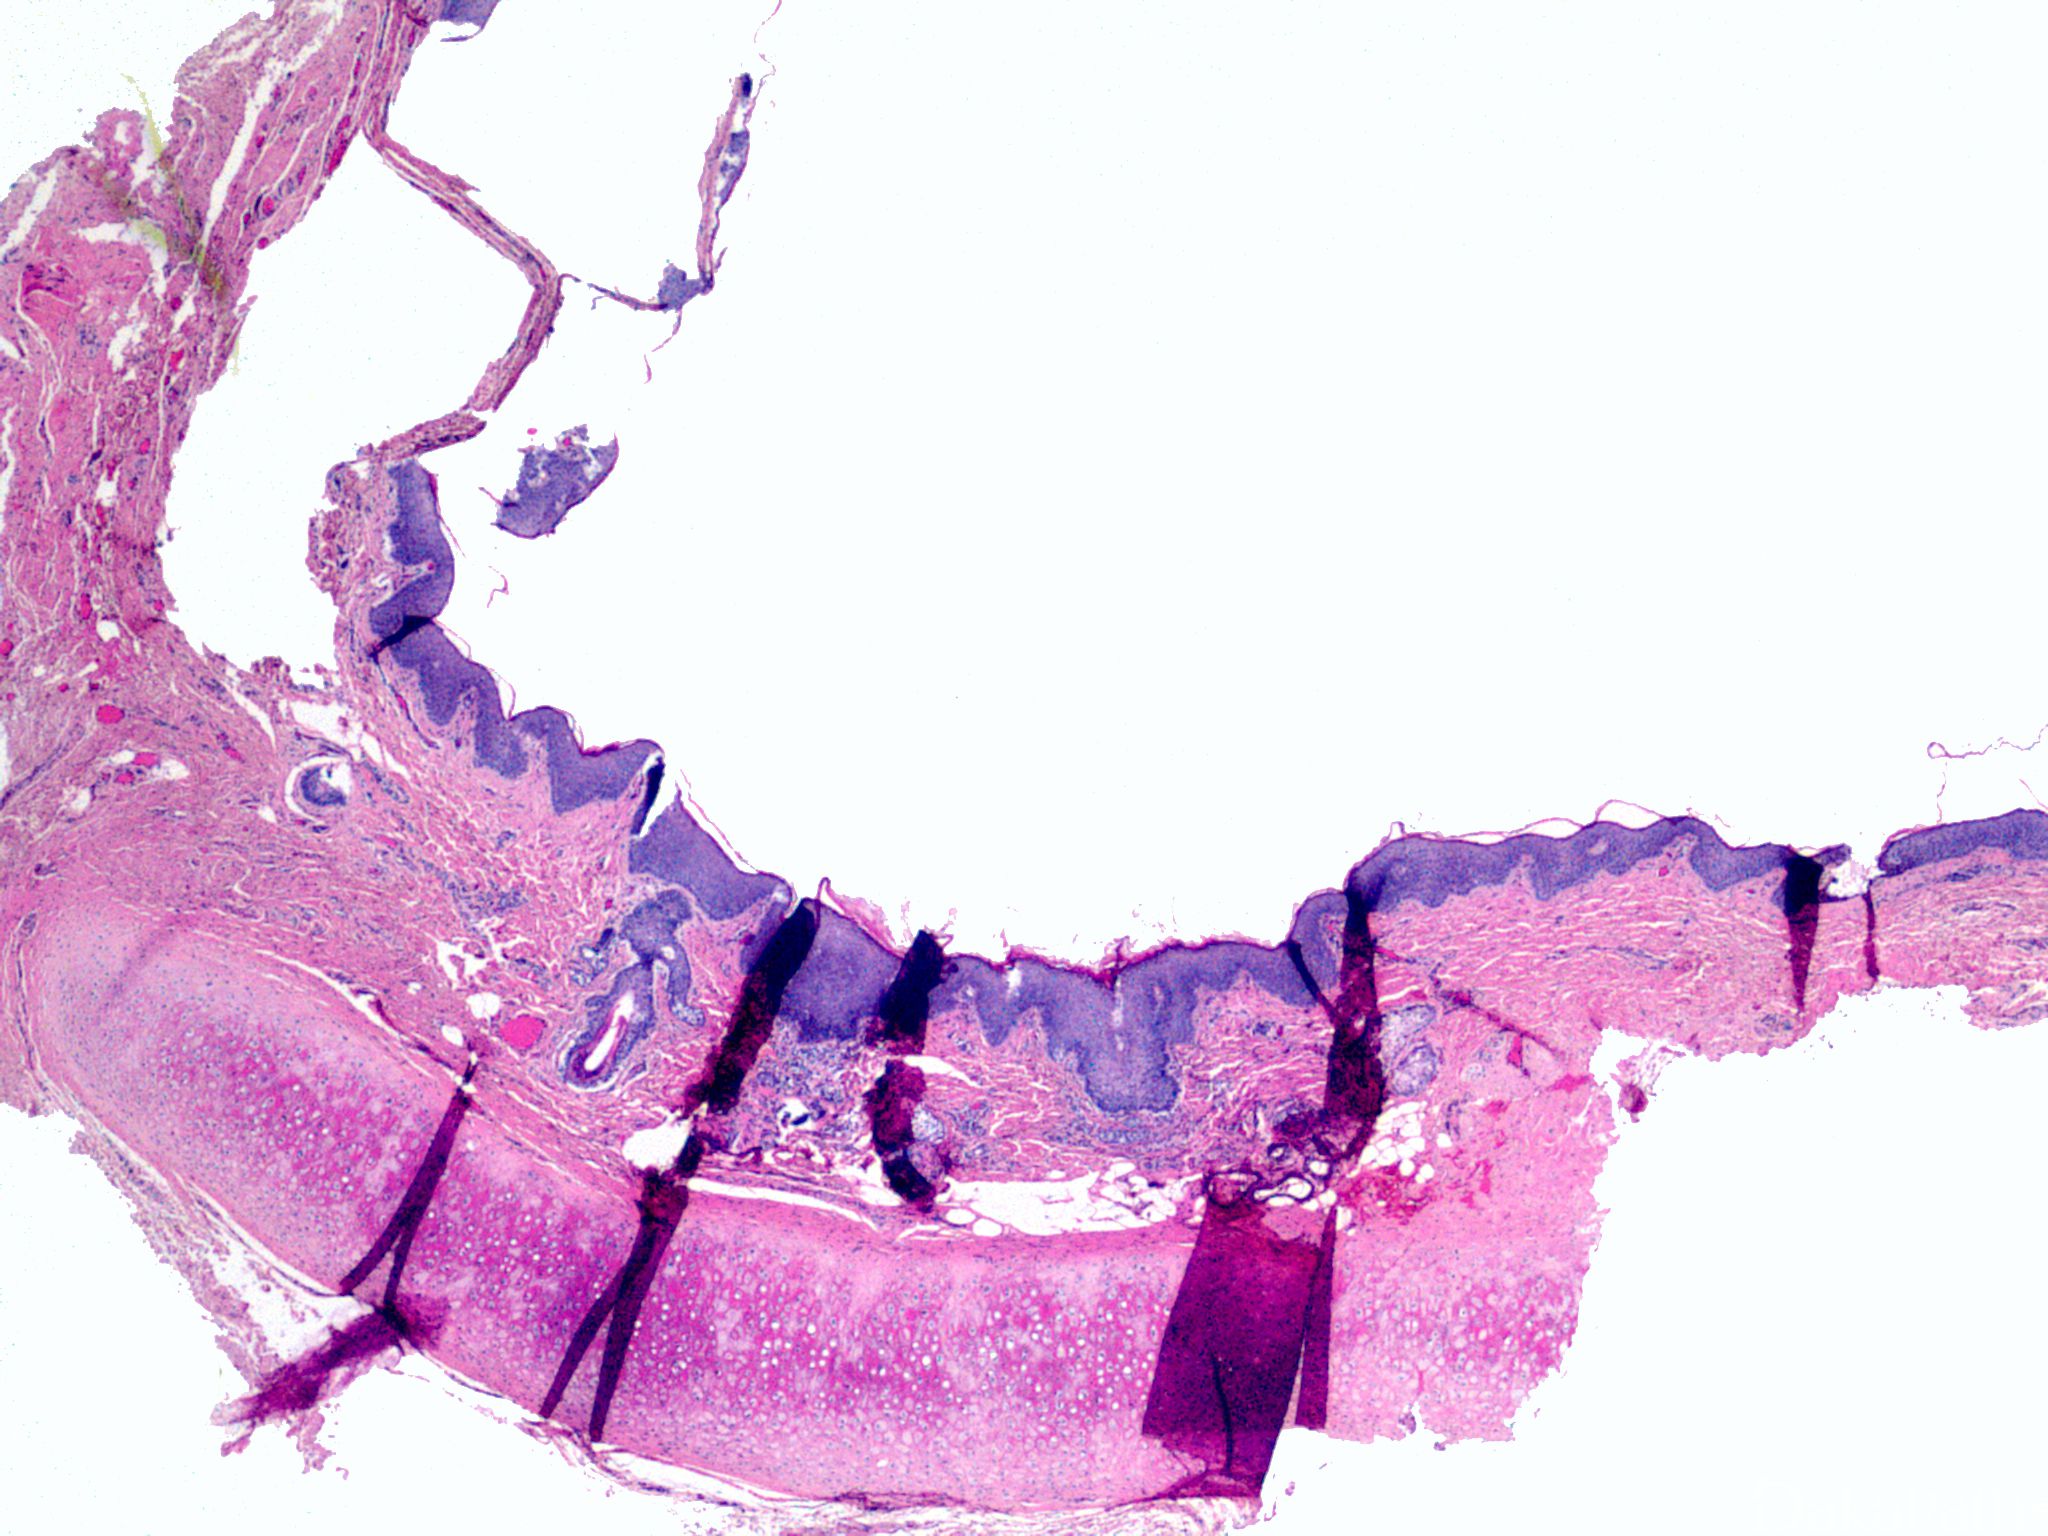

鳃裂囊肿

branchial cleft cyst